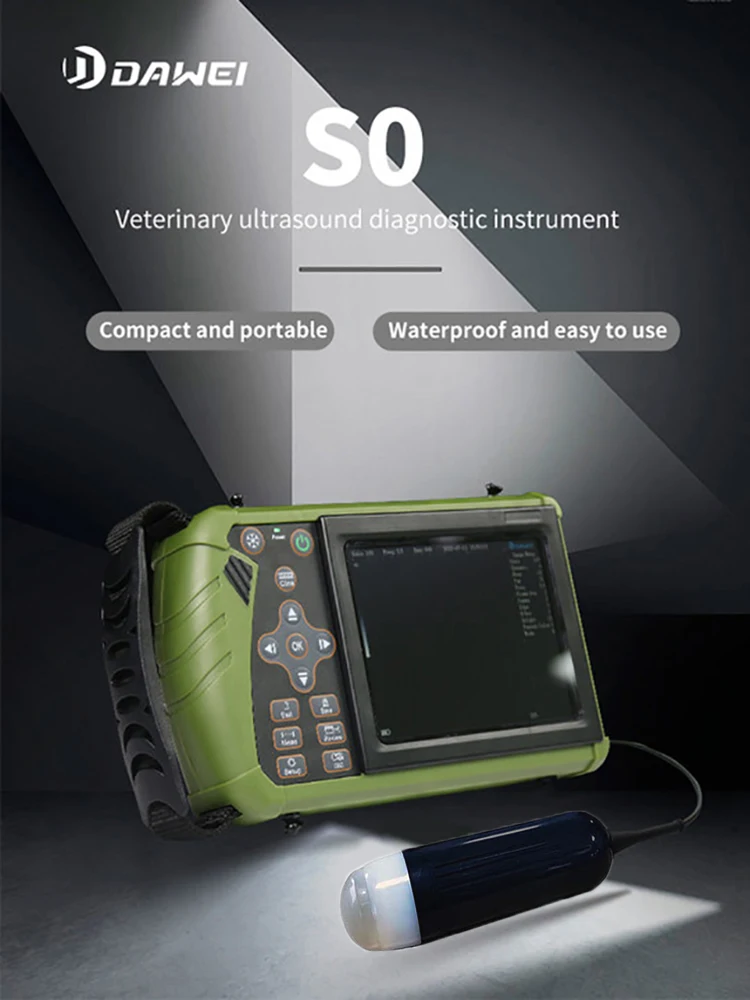

Small Full Digital Portable Ultrasound Equipment with Android/IOS Windows

This machine can be used for both humans and animals: